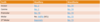

Draw a table to outline which instruments are used on which teeth